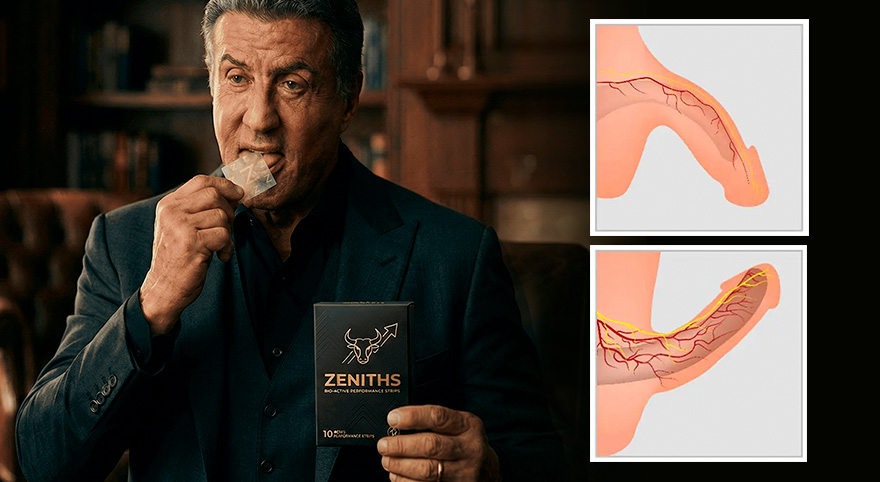

Elite Endorsements: The Secret Weapon of Hollywood and Pro Sports We reached out to some of the most demanding high-performers to put ZENITHS to the ultimate test.

Hollywood Action Legend, Sylvester Stallone:

"As I’ve gotten older, I demand efficiency, not waiting. ZENITHS is the most incredible thing I’ve seen; the speed of onset is unbelievable. It makes me feel like I’m back in my 30s. Every man needs this in his pocket."